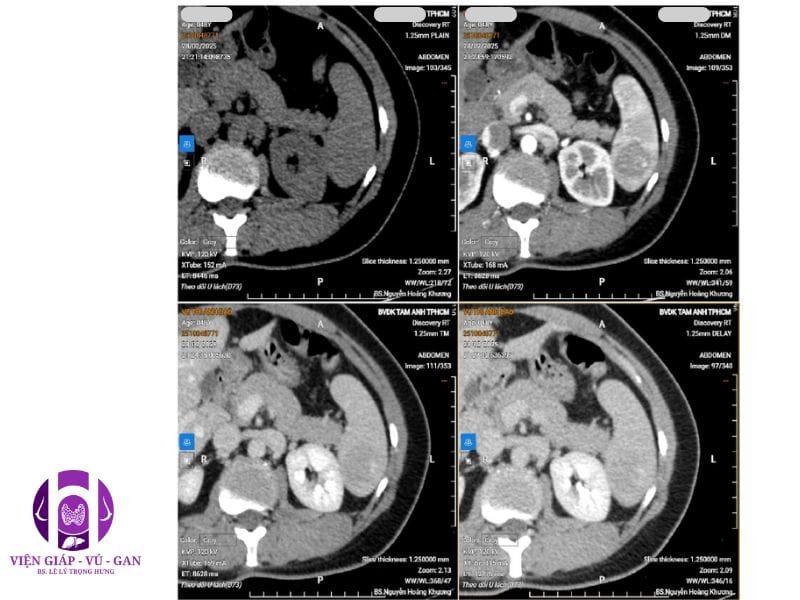

CTSCAN BỤNG CÓ THUỐC:

Lách: không to, tổn thương choán chỗ nhu mô cực dưới, giới hạn rõ, kích thước # 41x33x34mm, giảm nhẹ đậm độ trước tiêm, sau tiêm thuốc cản quang tổn thương bắt thuốc dạng chấm – nốt ở thì động mạch, lấp dần ở thì tĩnh mạch và thì muộn. Vỏ bao lách còn nguyên vẹn, không thâm nhiễm mỡ hay tụ dịch xung quanh.

CT:

• Khối giới hạn rõ, ngấm thuốc dạng chấm nốt ở ngoại vi không liên tục thì động mạch, ngấm dần vào trung tâm thì muộn.

• Nốt nhỏ có thể ngấm thuốc đồng nhất thì động mạch, giữ thuốc thì muộn.